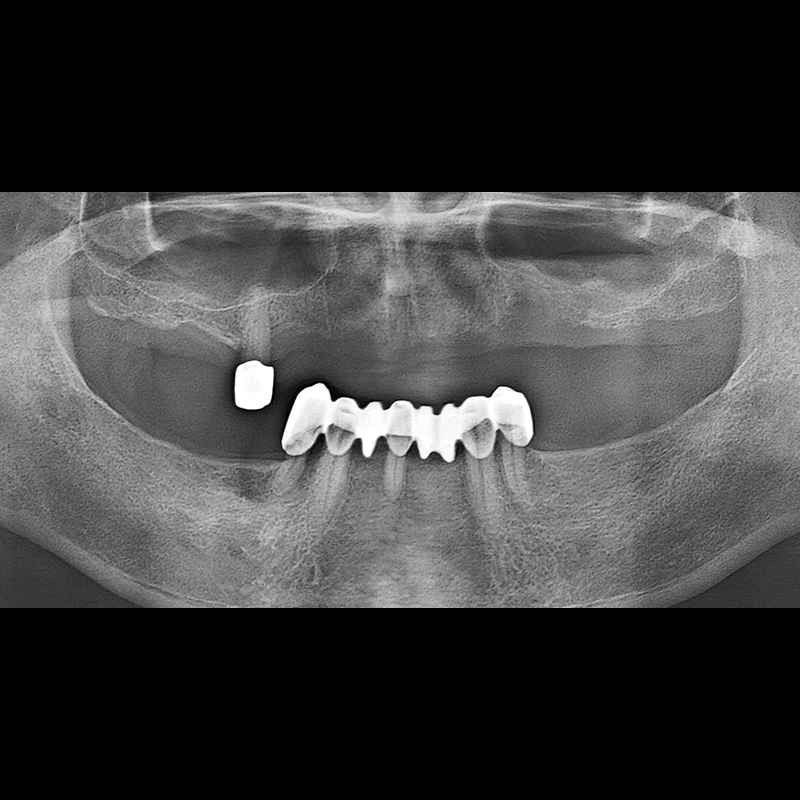

BEFORE AFTER

임플란트 전후사진 2025.05.30

결손된 치아 부분과 살리기 힘든 치아 위치에 임플란트를 식립하였습니다.